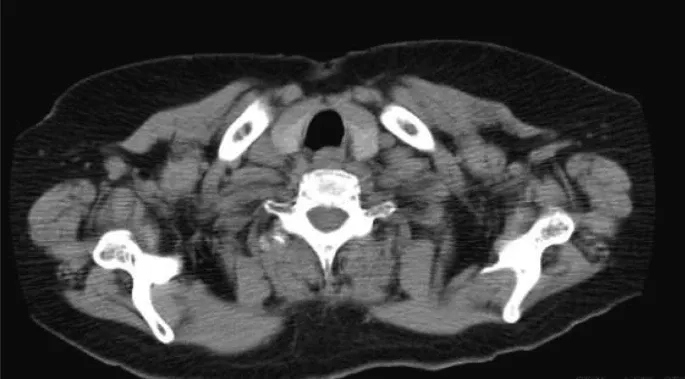

初诊时,右侧下颌下区可触及一个40×30 mm、弹性柔软、可移动的肿块,边界清晰,皮肤颜色健康。无自发性疼痛和压痛。MRI示圆形肿块,边界较清晰,大小为29×24×40 mm,前缘毗邻右侧颌下腺,后深部压迫右侧颈内静脉。边缘很光滑。肿块表现出高信号强度区域,部分伴随为内部的低信号区域。周围组织未见浸润,未见其他明显肿大淋巴结。基于这些发现,强烈怀疑涎腺肿瘤(图1a, b)。

图1. MRI的发现

CT及超声检查均未见异常(图3)。经与本院内分泌外科会诊,2个月行超声引导下细针穿刺活检2次;但在甲状腺中未检测到癌成分。一般来说,隐匿性甲状腺癌的颈部淋巴结转移病例需要全甲状腺切除术。然而,考虑到本例患者PTC进展缓慢、患者年龄、既往有慢性心功能不全、高血压、糖尿病、哮喘病史及整体身体状况,内分泌外科医生未能获得患者的知情同意;因此,对该患者选择密切观察随访。手术后8年,未见颈部肿瘤复发或甲状腺癌大小变化,患者进展良好。

图3. CT结果